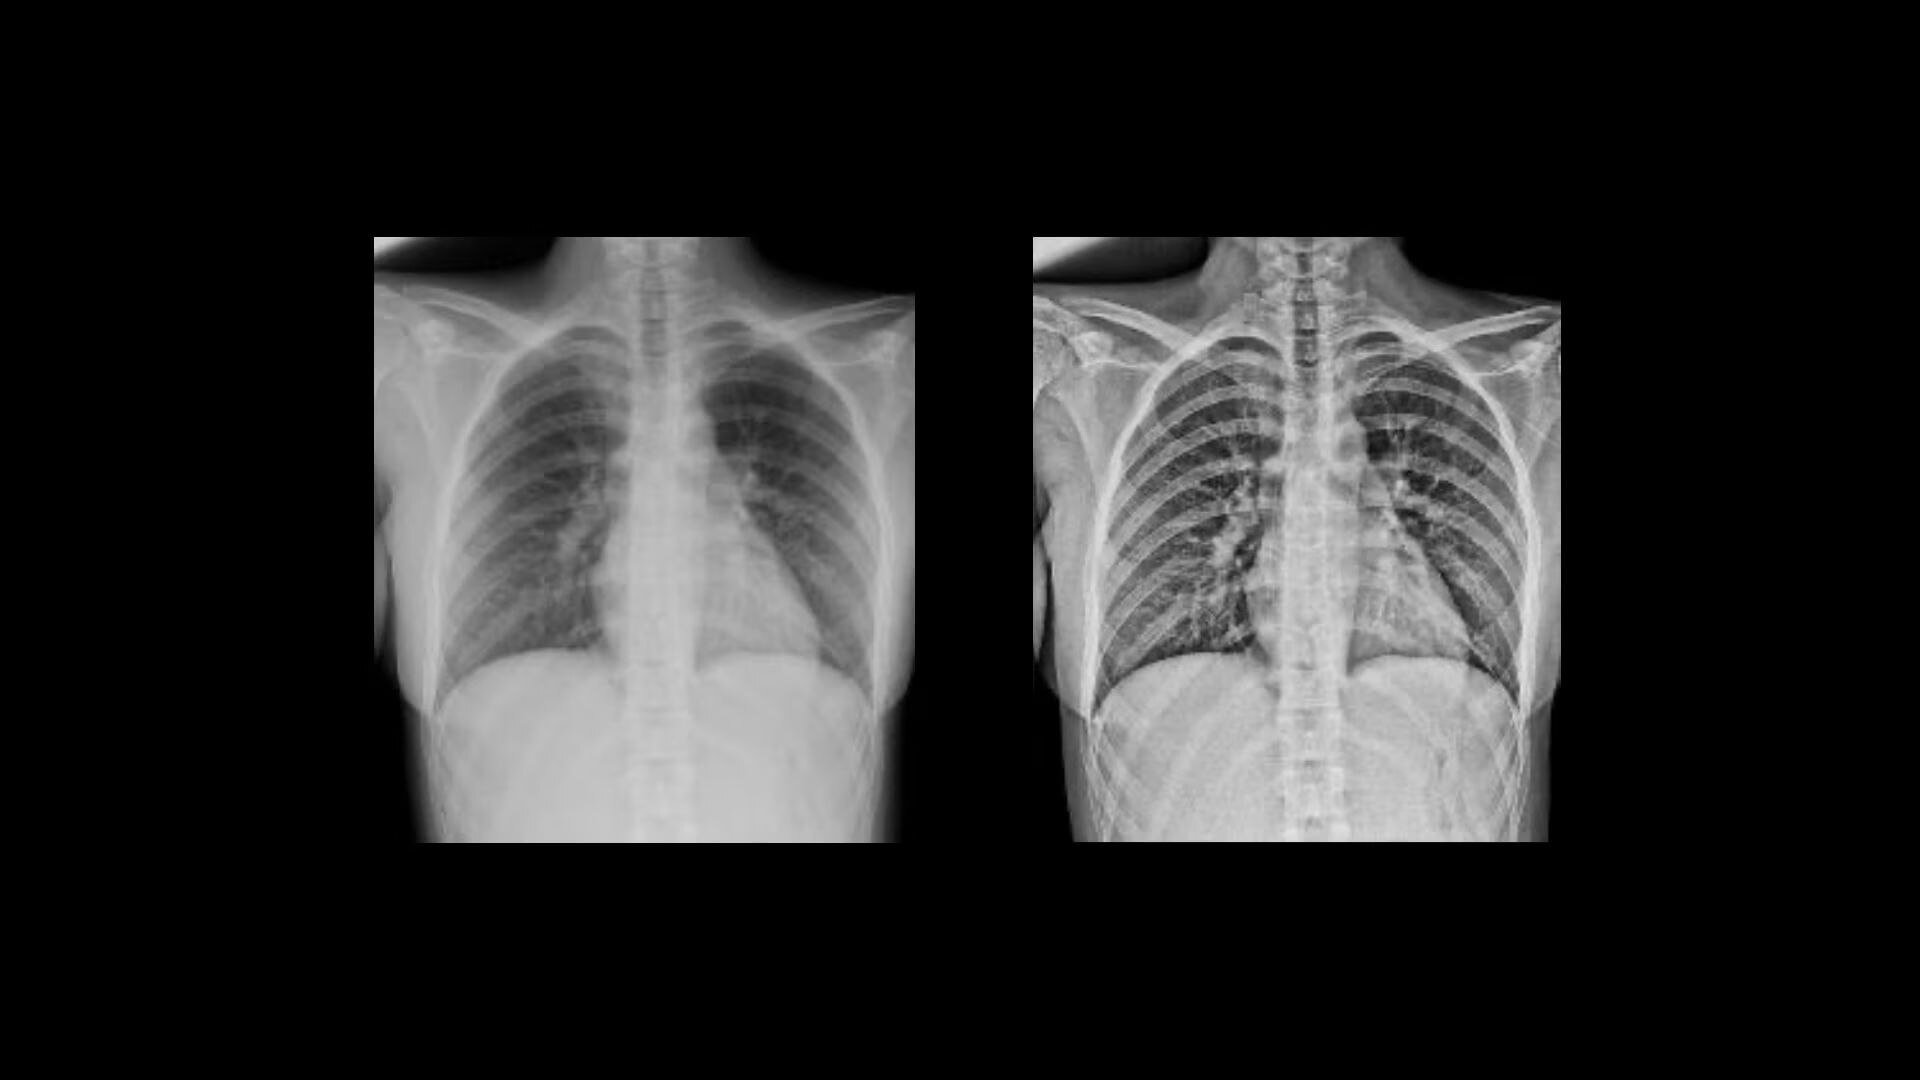

Clarity

Improve visualization and detail

Local Contrast Enhancement (LCE) increases local contrast in both pediatric and adult chest X-ray images for better visualization of the lungs, heart, and spine regions. It is also available for ankle joint (AP), foot (AP), and patella (tangential)*, and has three levels of enhancement (low, medium and high).